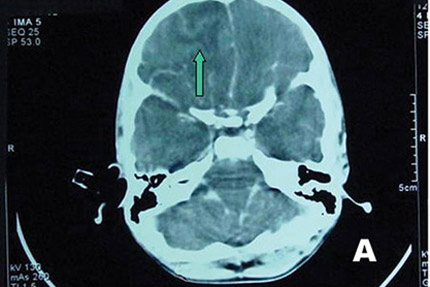

Tại BV Bệnh Nhiệt đới, BN sốt 39oC, lơ mơ, cổ cứng, thở nhanh 30 lần/phút. Kết quả xét nghiệm soi dịch não tủy không thấy có vi trùng lao hay vi nấm gây viêm màng não nhưng lại có sự hiện diện của một loại amip.

Sau khi anh T. tử vong, BV Bệnh Nhiệt đới tiếp tục làm nhiều xét nghiệm và kết quả xét nghiệm sinh học phân tử PCR cho thấy anh tử vong do “amip ăn não người” tấn công.

Theo bác sĩ Huỳnh Hồng Quang, chuyên gia trong lĩnh vực ký sinh sinh trùng cho biết: Naegleria fowleri ăn não người một khi chui vào não thông qua đường mũi sẽ nhanh chóng kết liễu nạn nhân trong thời gian ngắn nhất.

Naegleria fowleri nhiễm vào người thông qua mũi xoang, len lỏi dần đến tế bào thần kinh khứu giác để tìm đường xâm nhập vào não bộ vật chủ.